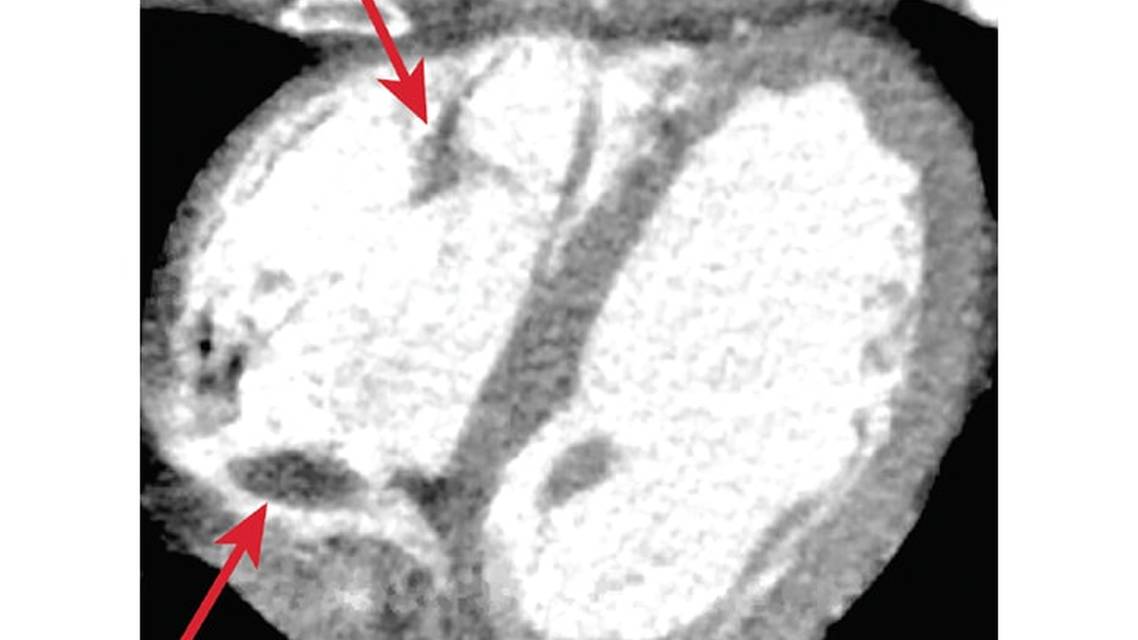

There are other diagnostic tests to consider in this population. If there is clinical suspicion based on history and examination, or if infarcts appear embolic and span multiple vascular territories, and the individual has an intracardiac shunt, peripheral venous duplex ultrasound is recommended. If infarcts appear embolic in the setting of known or suspected valve disease, including endocarditis or hypercoagulability a transesophageal echocardiogram (TEE) should be considered because it offers a better view of posterior cardiac structures. Cardiac CT is noninvasive and can offer comparable diagnostic information as TEE, depending on the indication.